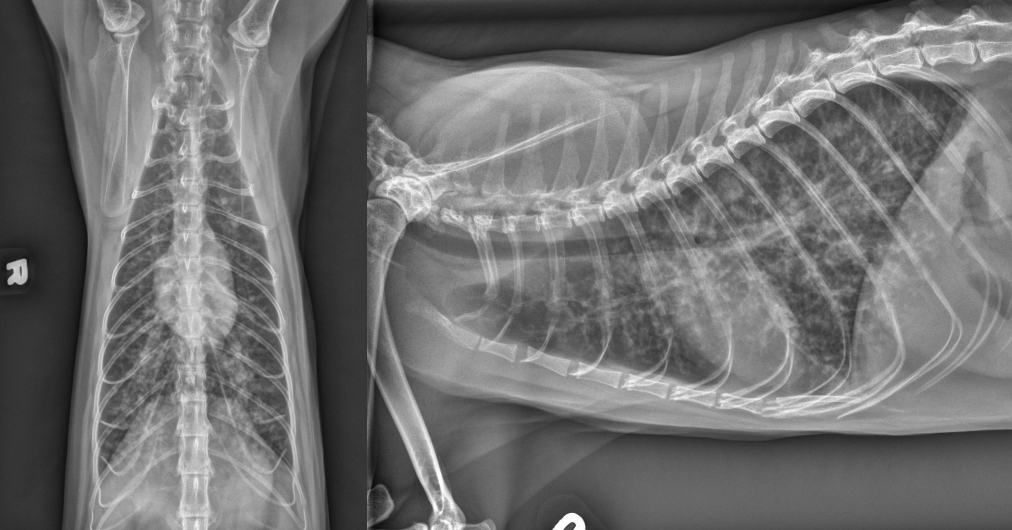

● 13 yo mixed breed female dog

● Right forelimb lameness

nodular pattern -> metastases

lytic changes in rib seen in VD image